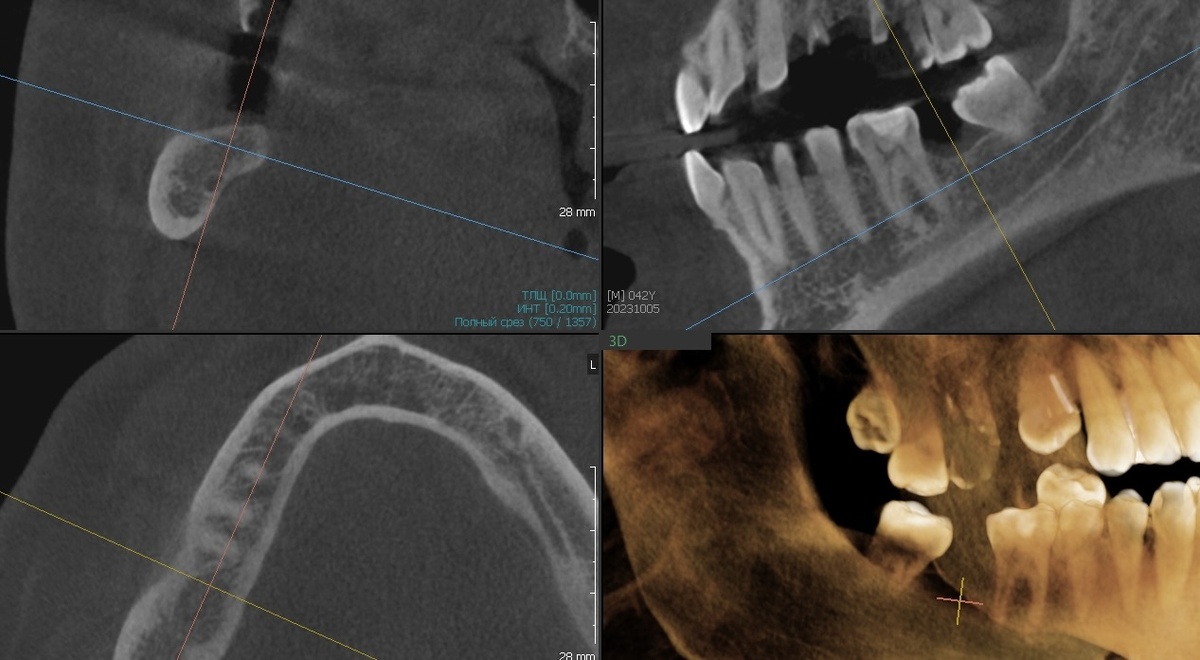

КТ после установки:

Srraumann TL

Имплантат не доходит до канала нижнечелюстного нерва 1,6 мм. По рекомендациям оптимальное расстояние - не менее 2 мм. Мы в пограничной, но контролируемой зоне.